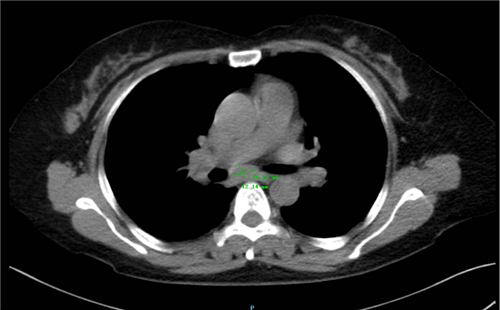

患者是一位 55 岁的女性,向来生活作息规律。3 天前,她因后背部疼痛不适前往外院检查,发现肺部存在结节。为进一步明确诊断与治疗,患者来到我院呼吸与危重症医学一科就诊。胸部 CT 检查显示,患者两肺有结节,同时纵膈淋巴结(7 组)肿大。